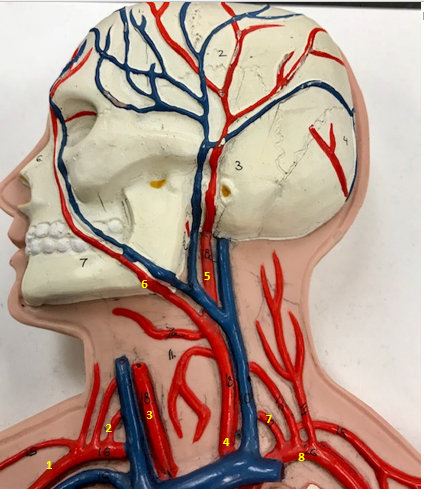

Right subclavian artery

Name #1

Supplies blood to right arm and shoulder

Function of right subclavian artery (1)

Right vertebral artery

Name #2

Supplies blood to brain and spinal cord

Function of right vertebral artery (2)

Right common carotid artery

Name #3

Supplies blood to right neck and head

Function of right common carotid artery (3)

Left common carotid artery

Name #4

Supplies blood to left neck and head

Function of left common carotid artery (4)

Left external carotid artery

Name #5

Supplies blood to face neck and skull

Function left external carotid artery (5)

Left facial artery

Name #6

Supplies blood to face and neck

Function of left facial artery (6)

Left vertebral artery

Name #7

Supplies blood to brain and spinal cord

Function of left vertebral artery (7)

Left subclavian artery

Name #8

Supplies blood to left arm and shoulder

Function of left subclavian artery (8)